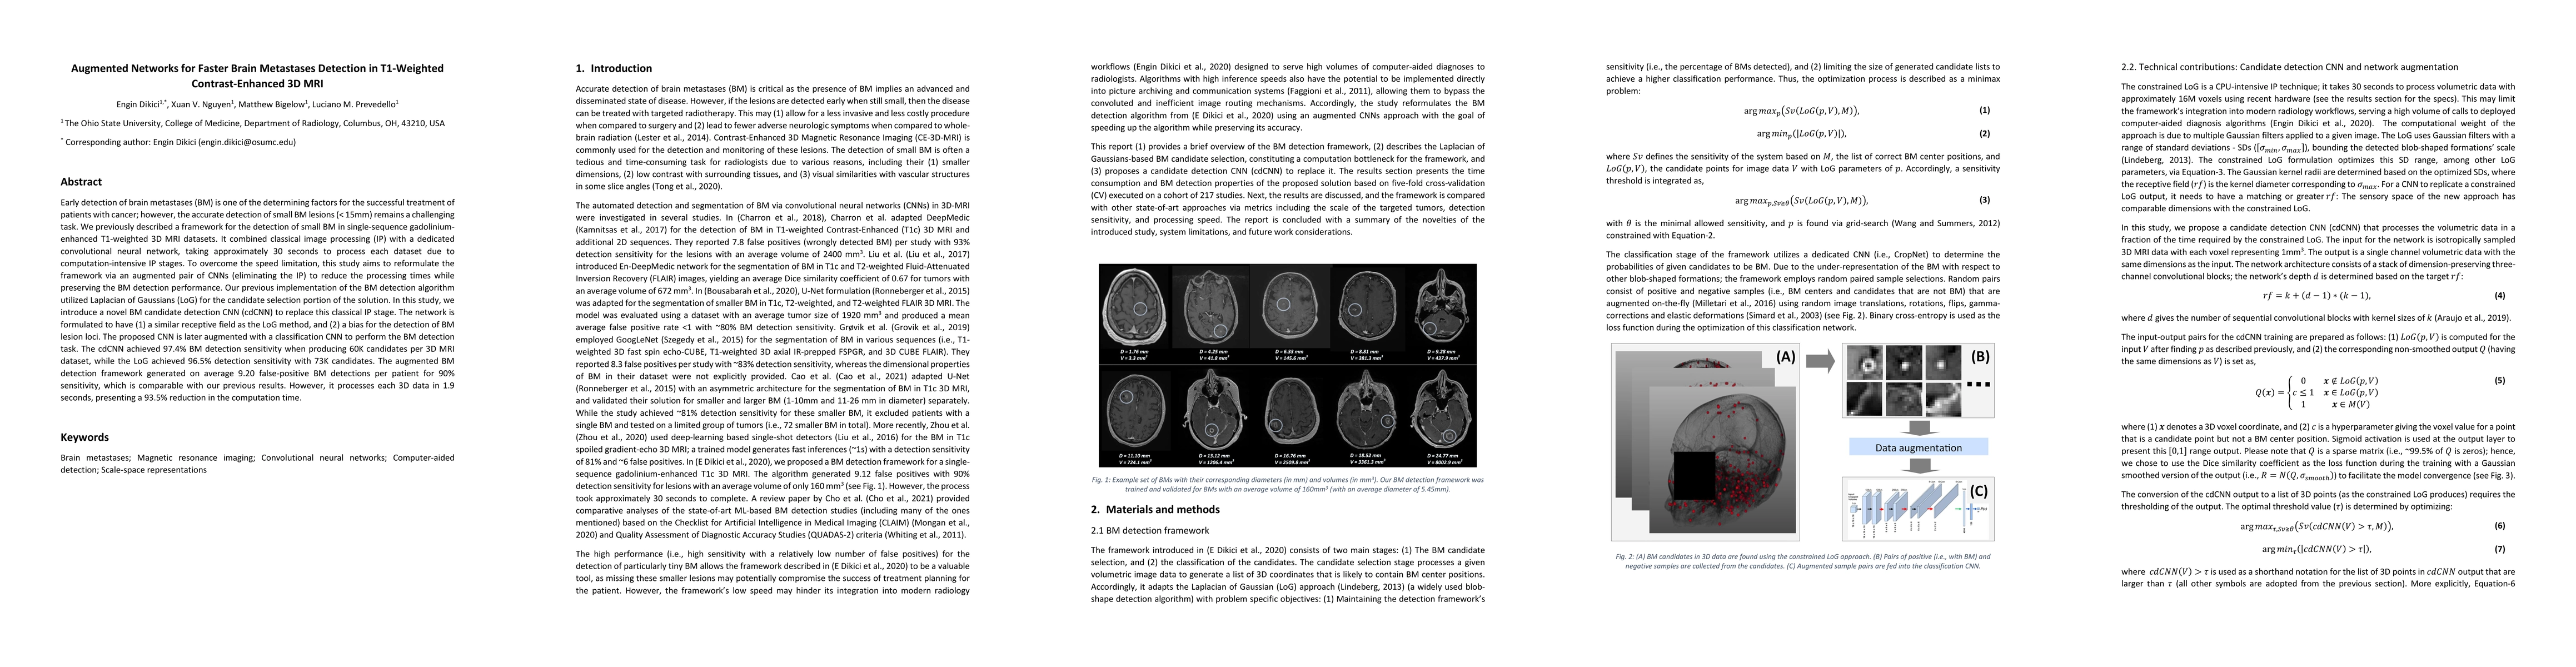

Early detection of brain metastases (BM) is one of the determining factors for the successful treatment of patients with cancer; however, the accurate detection of small BM lesions (< 15mm) remains a challenging task. We previously described a framework for the detection of small BM in single-sequence gadolinium-enhanced T1-weighted 3D MRI datasets. It combined classical image processing (IP) with a dedicated convolutional neural network, taking approximately 30 seconds to process each dataset due to computation-intensive IP stages. To overcome the speed limitation, this study aims to reformulate the framework via an augmented pair of CNNs (eliminating the IP) to reduce the processing times while preserving the BM detection performance. Our previous implementation of the BM detection algorithm utilized Laplacian of Gaussians (LoG) for the candidate selection portion of the solution. In this study, we introduce a novel BM candidate detection CNN (cdCNN) to replace this classical IP stage. The network is formulated to have (1) a similar receptive field as the LoG method, and (2) a bias for the detection of BM lesion loci. The proposed CNN is later augmented with a classification CNN to perform the BM detection task. The cdCNN achieved 97.4% BM detection sensitivity when producing 60K candidates per 3D MRI dataset, while the LoG achieved 96.5% detection sensitivity with 73K candidates. The augmented BM detection framework generated on average 9.20 false-positive BM detections per patient for 90% sensitivity, which is comparable with our previous results. However, it processes each 3D data in 1.9 seconds, presenting a 93.5% reduction in the computation time.